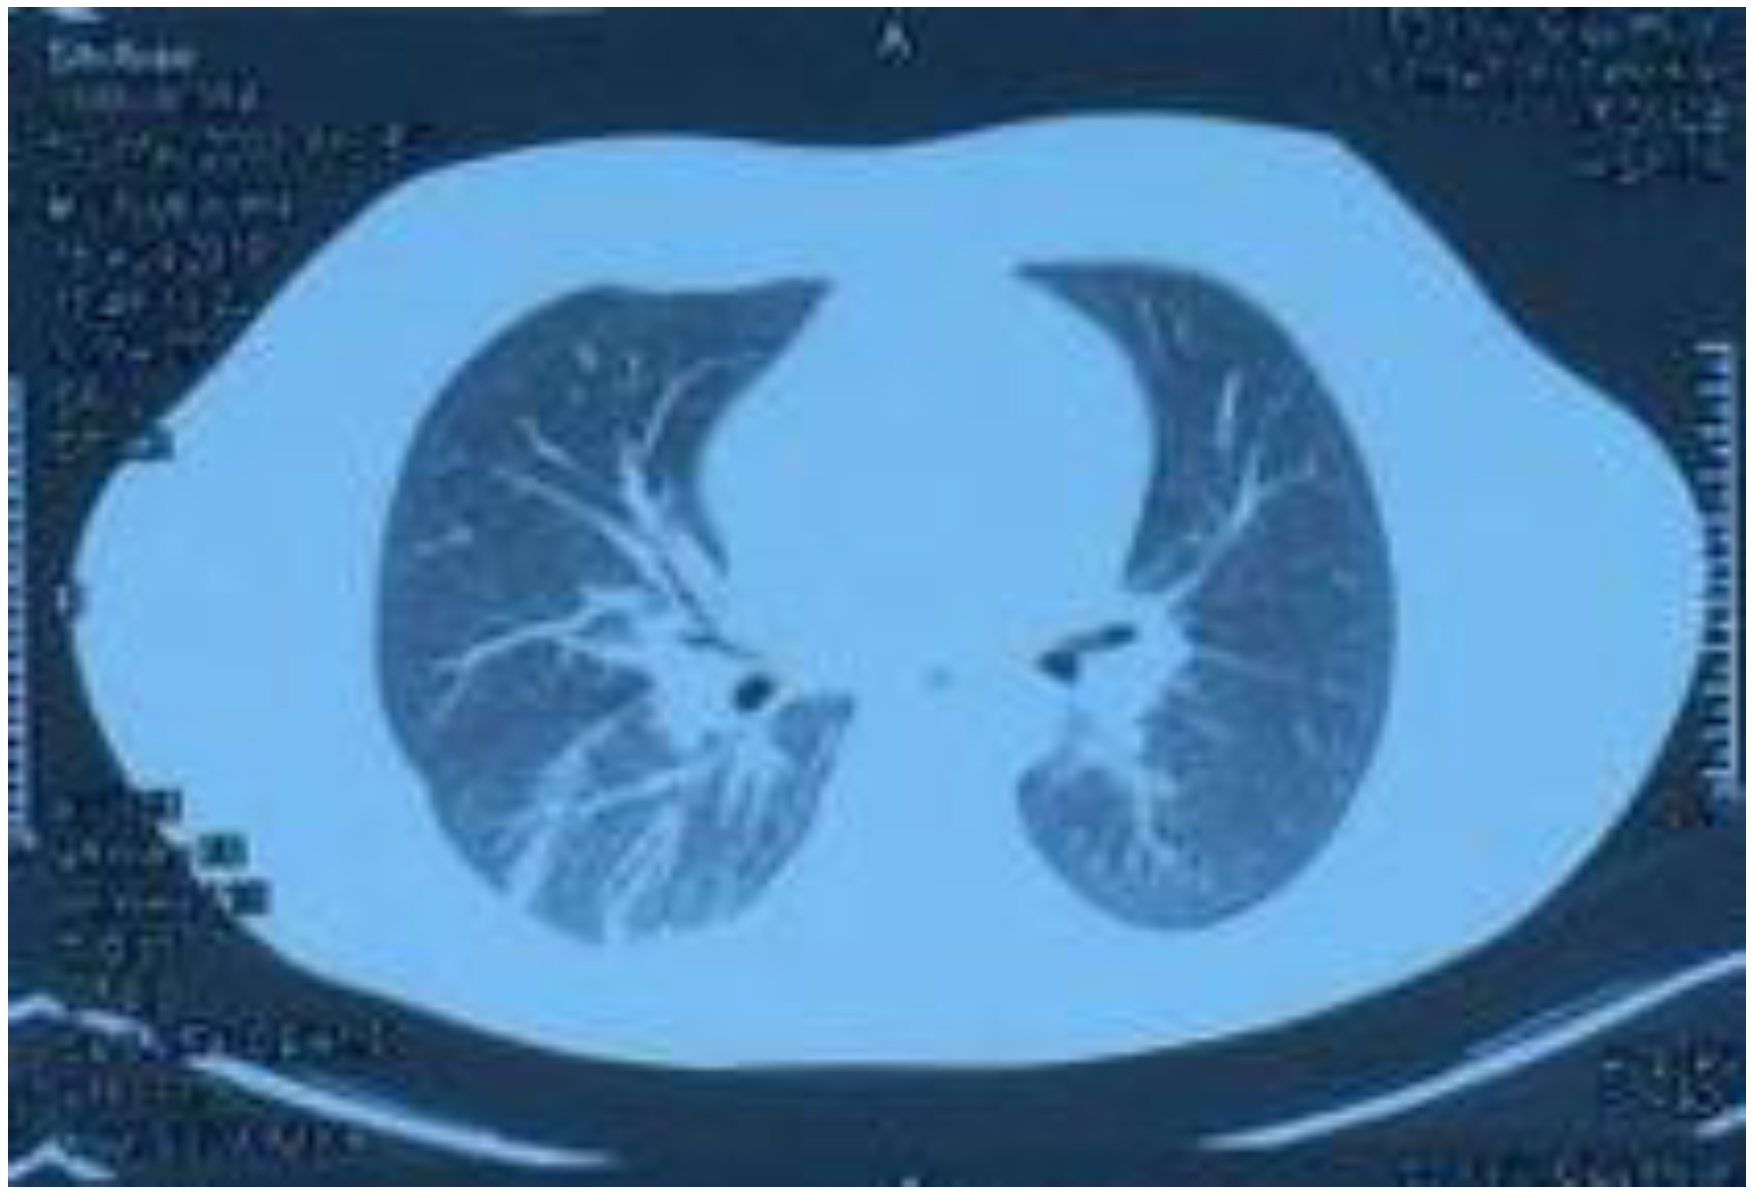

Lung CT performed on 15 August 2018, showing increased texture in both lungs, a patchy high-density shadow, unobstructed bronchi above the segment, and a patchy high-density shadow in the posterior segment of the lower lobe of the right lung.

On 15 August, the patient started coughing up yellow phlegm and had another fever spike; the highest reading reaching 38.9 °C. Sputum cultures and chest computed tomography examination were performed (Figure 4). The culture test results showed Pseudomonas aeruginosa and Escherichia coli growth. Consequently, the drug regimen was adjusted to imipenem 500 mg IV infusion Q 6 h according to the drug sensitivity test. The CT results showed increased texture of both lungs, a patchy high-density shadow, unobstructed bronchi above the segment, and a patchy high-density shadow of the lower and posterior segment of the right lung. Other laboratory tests revealed white blood cells, 7.12 × 109/L; neutrophils ratio, 67.10%; red blood cells, 3.92 × 1012/L; platelets, 248 × 109/L; serum myoglobin, 111.60 ng/mL; creatine kinase isoenzyme, 7.30 ng/mL; serum hypersensitive troponin I, 356.79 ng/L; and NT-probNP, 594.70 pg/mL. (Table 1) The patient’s symptoms significantly improved after weaning and adjusting antibiotics, and his body temperature gradually normalized. On 20 August, drug administration was stopped, and the patient’s condition improved; therefore, he was discharged. After discharge, he continued to take Jinshuibao and Qishen Yiqi pills orally.